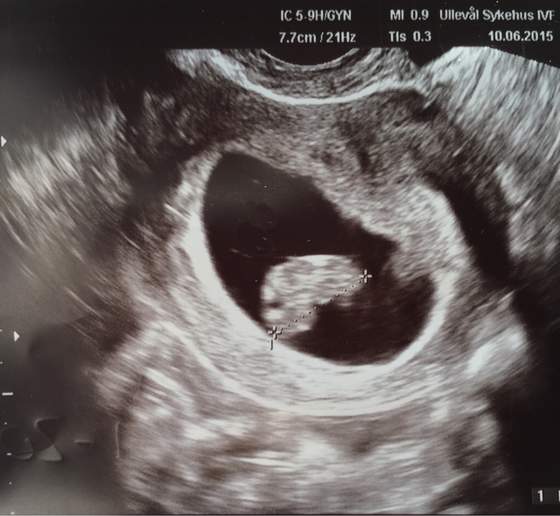

Byłam dziś na pobraniu krwi i po wycieczce znowu- kamień w brzuchu. W piątek mam jechać na drugie badanie. Jeśli będzie wzrastać to będę się upierać żeby mi pomogli utrzymać ciąże. Jutro zadzwonię o wynik.

Sama sobie zwiększyłam dawkę Lutinusa do 400/dobę. Oni tu maja dziwne podejście w NO, selekcja naturalna...